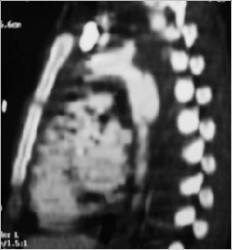

Because the bleeding was contained and she has just a little hemodynamic instability, the choice was endovascular treatment of traumatic thoracic aortic rupture.

A CT Scan was ordered preoperatory: